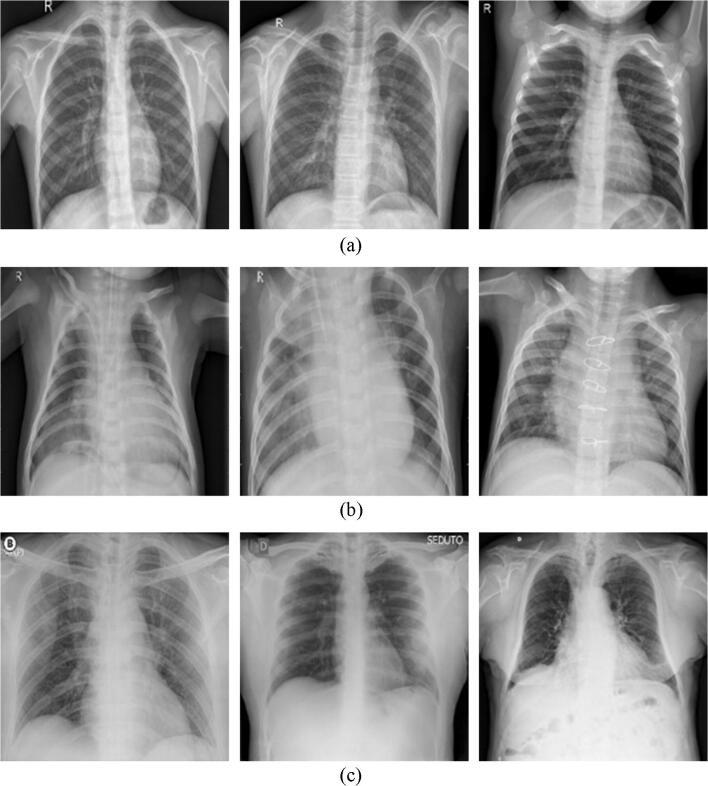

The recent novel coronavirus (also known as COVID-19) has rapidly spread worldwide, causing an infectious respiratory disease that has killed hundreds of thousands and infected millions. While test kits are used for diagnosis of the disease, the process takes time and the test kits are limited in their availability. However, the COVID-19 disease is also diagnosable using radiological images taken through lung X-rays. This process is known to be both faster and more reliable as a form of identification and diagnosis. In this regard, the current study proposes an expert-designed system called COVIDetectioNet model, which utilizes features selected from combination of deep features for diagnosis of COVID-19. For this purpose, a pretrained Convolutional Neural Network (CNN)-based AlexNet architecture that employed the transfer learning approach, was used. The effective features that were selected using the Relief feature selection algorithm from all layers of the architecture were then classified using the Support Vector Machine (SVM) method. To verify the validity of the model proposed, a total of 6092 X-ray images, classified as Normal (healthy), COVID-19, and Pneumonia, were obtained from a combination of public datasets. In the experimental results, an accuracy of 99.18% was achieved using the model proposed. The results demonstrate that the proposed COVIDetectioNet model achieved a superior level of success when compared to previous studies.

最近的新型冠状病毒(也称为COVID-19)已在全球迅速传播,引发了一种传染性呼吸道疾病,导致数十万人死亡,数百万人感染。虽然检测试剂盒用于该疾病的诊断,但这个过程需要时间,而且检测试剂盒的供应有限。然而,COVID-19疾病也可以通过肺部X光拍摄的放射图像进行诊断。众所周知,作为一种识别和诊断形式,这个过程更快且更可靠。在这方面,当前的研究提出了一种由专家设计的系统,称为COVIDetectioNet模型,该模型利用从深度特征组合中选择的特征来诊断COVID-19。为此,使用了采用迁移学习方法的基于预训练卷积神经网络(CNN)的AlexNet架构。然后,使用支持向量机(SVM)方法对从该架构的所有层中使用Relief特征选择算法选择的有效特征进行分类。为了验证所提出模型的有效性,从公共数据集的组合中获得了总共6092张X光图像,分为正常(健康)、COVID-19和肺炎三类。在实验结果中,所提出的模型实现了99.18%的准确率。结果表明,与先前的研究相比,所提出的COVIDetectioNet模型取得了更高的成功水平。